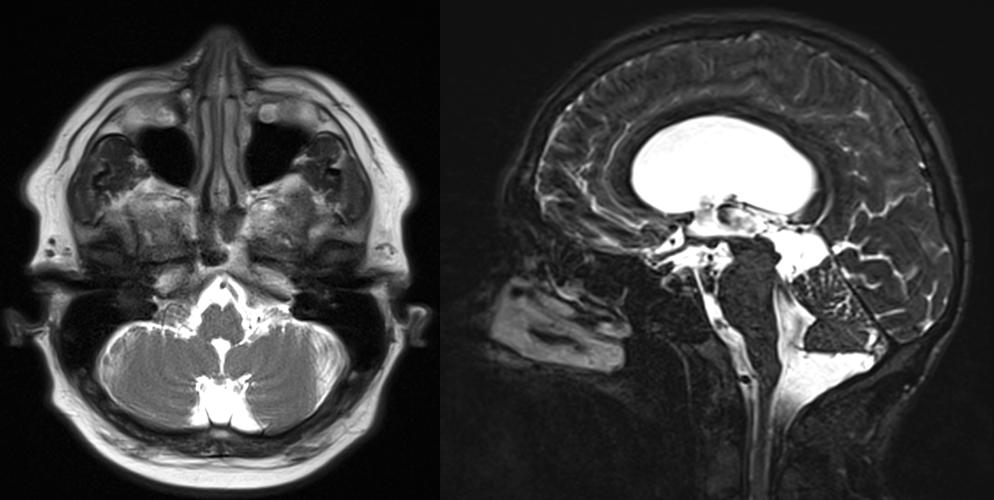

Imagistica este esențială pentru identificarea chistelor arahnoidiene:

- RMN (rezonanță magnetică nucleară): metoda preferată, evidențiază conținutul de LCR și raporturile cu structurile cerebrale.

Chistul arahnoidian apare ca o leziune hipointensă pe imaginile T1 și hiperintensă pe imaginile T2, cu semnal identic cu cel al lichidului cefalorahidian.